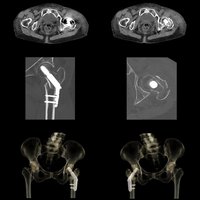

Bei dem Volumen-CT Aquilion One PRISM Edition von Canon Medical handelt es sich um einen einzigartigen HighEnd-Computertomographen. Er setzt während der DualEnergy-Akquisition und der Datenrekonstruktion neue Maßstäbe und greift in der spektralen Bildgebung auf die Deep-Learning-Rekonstruktion AiCE zurück.

Auch für virtuelle monochromatische Bilder mit 35 keV – 135 keV, die Reduktion von Beam-Hardening-Artefakten, Knochenentfernungen, die Bestimmung der Ordnungszahl, Electron-Density-Bestimmungen und viele andere Anwendungen bietet der Aquilion One PRISM Edition das optimale Gerät.

Mit AiCE, kurz für Advanced intelligent Clear-IQ Engine, kann der Aquilion One PRISM Edition besonders scharfe, klare und präzise Bilder in kürzester Zeit gewinnen. Die KI unterstützt die Reduktion von Bildrauschen auf ein Minimum und ermöglicht klare Aufnahmen mit sehr gut erkennbaren Strukturen auch bei niedrigem Kontrast. Gleichzeitig bringt sie eine automatische Anpassung des Kontrasts mit sich. Weiterhin ermöglicht sie eine schnelle kV-Umschaltung und eine patientenspezifische mA-Modulation, die wiederum mit einer Deep Learning-Rekonstruktion kombiniert wird, um eine hervorragende Energietrennung zu erzielen und Bildrauschen weiter zu reduzieren.